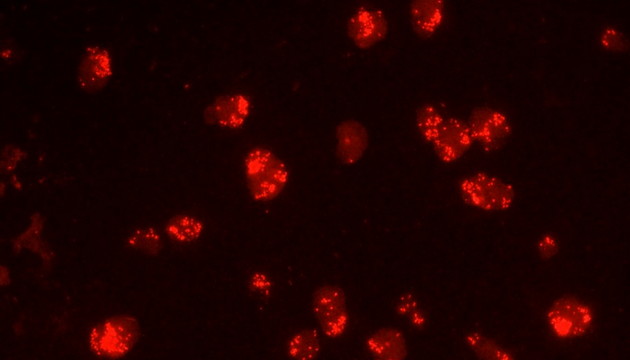

熒光原位雜交(Fluorescence In Situ Hybridization,F(xiàn)ISH)是臨床病理檢測(cè)中廣泛運(yùn)用的一種分子細(xì)胞遺傳學(xué)診斷技術(shù),其原理是用熒光染料直接或間接標(biāo)記的DNA核酸探針與待測(cè)樣本中的DNA核酸序列按照堿基互補(bǔ)配對(duì)的原則進(jìn)行雜交,然后通過(guò)熒光顯微鏡觀察熒光信號(hào)位置、數(shù)量等來(lái)判斷待測(cè)序列的缺失、擴(kuò)增及易位等情況。其高分辨率、直接反映異常細(xì)胞比例、快速簡(jiǎn)便的特點(diǎn),使其成為臨床檢測(cè)、預(yù)后評(píng)估及用藥指導(dǎo)的重要工具。

FISH技術(shù)面臨熒光弱、背景噪聲、多通道疊加等難點(diǎn)。為了保障熒光信號(hào)強(qiáng)度,一般需要用到研究級(jí)熒光顯微鏡,半復(fù)消色差或以上的物鏡,以及高功率的LED熒光光源或汞燈光源;為了去除背景噪聲,一般需要搭配高截止深度的濾光片和高靈敏度相機(jī);多通道疊加時(shí)要提取紅綠信號(hào)點(diǎn),然后放到藍(lán)色DAPI信號(hào)上,處理需要相當(dāng)?shù)募记伞?